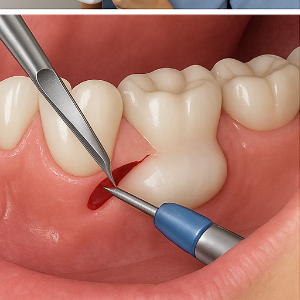

제거 방법은 보통 다음과 같이 진행돼요:

- 잇몸을 절개해서 뼈 돌출 부위를 드러내고

- 드릴이나 버를 사용해 뼈를 깎거나 다듬어서

- 잇몸을 다시 봉합하는 방식이에요 .